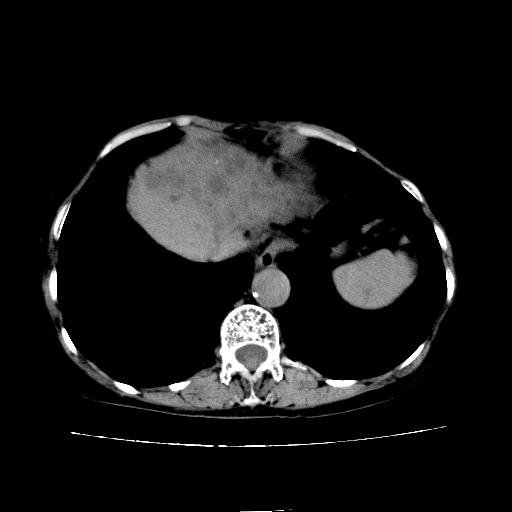

静脉期

看片子胆管里结石,肝上显示的占位会不会是胆管癌?大家帮忙看看,图像不太好,手头的处理文件没有,大致转换了一下,有原始图像数据

考虑胆管结石伴左肝内胆管扩张,不除外胆管细胞癌。

1)考虑肝左叶胆管细胞癌并肝内转移。2)肝左叶肝内胆管结石。